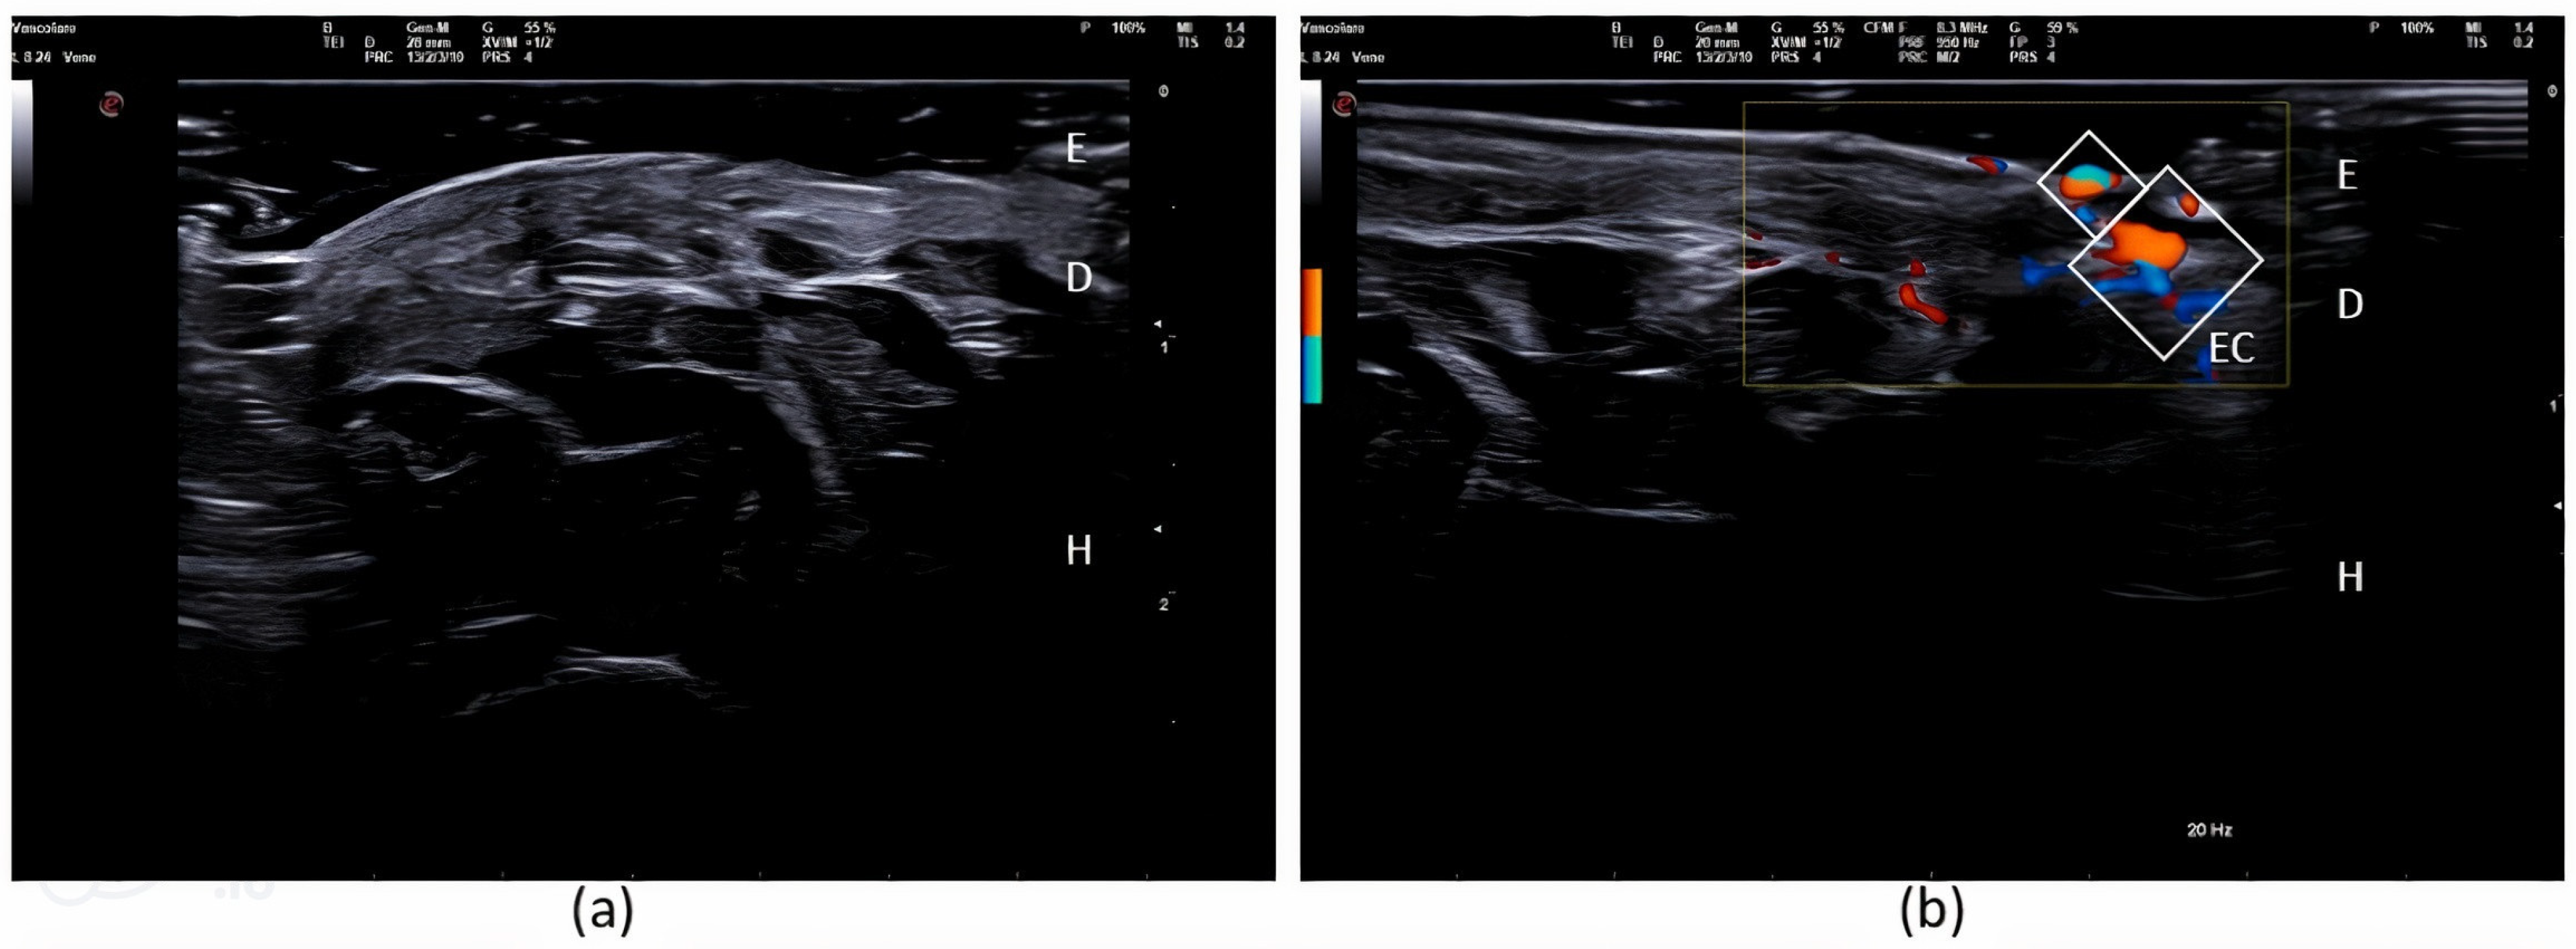

2. Case Report

| 2024 | Our Case | F | 29 | 19 | Left sole |